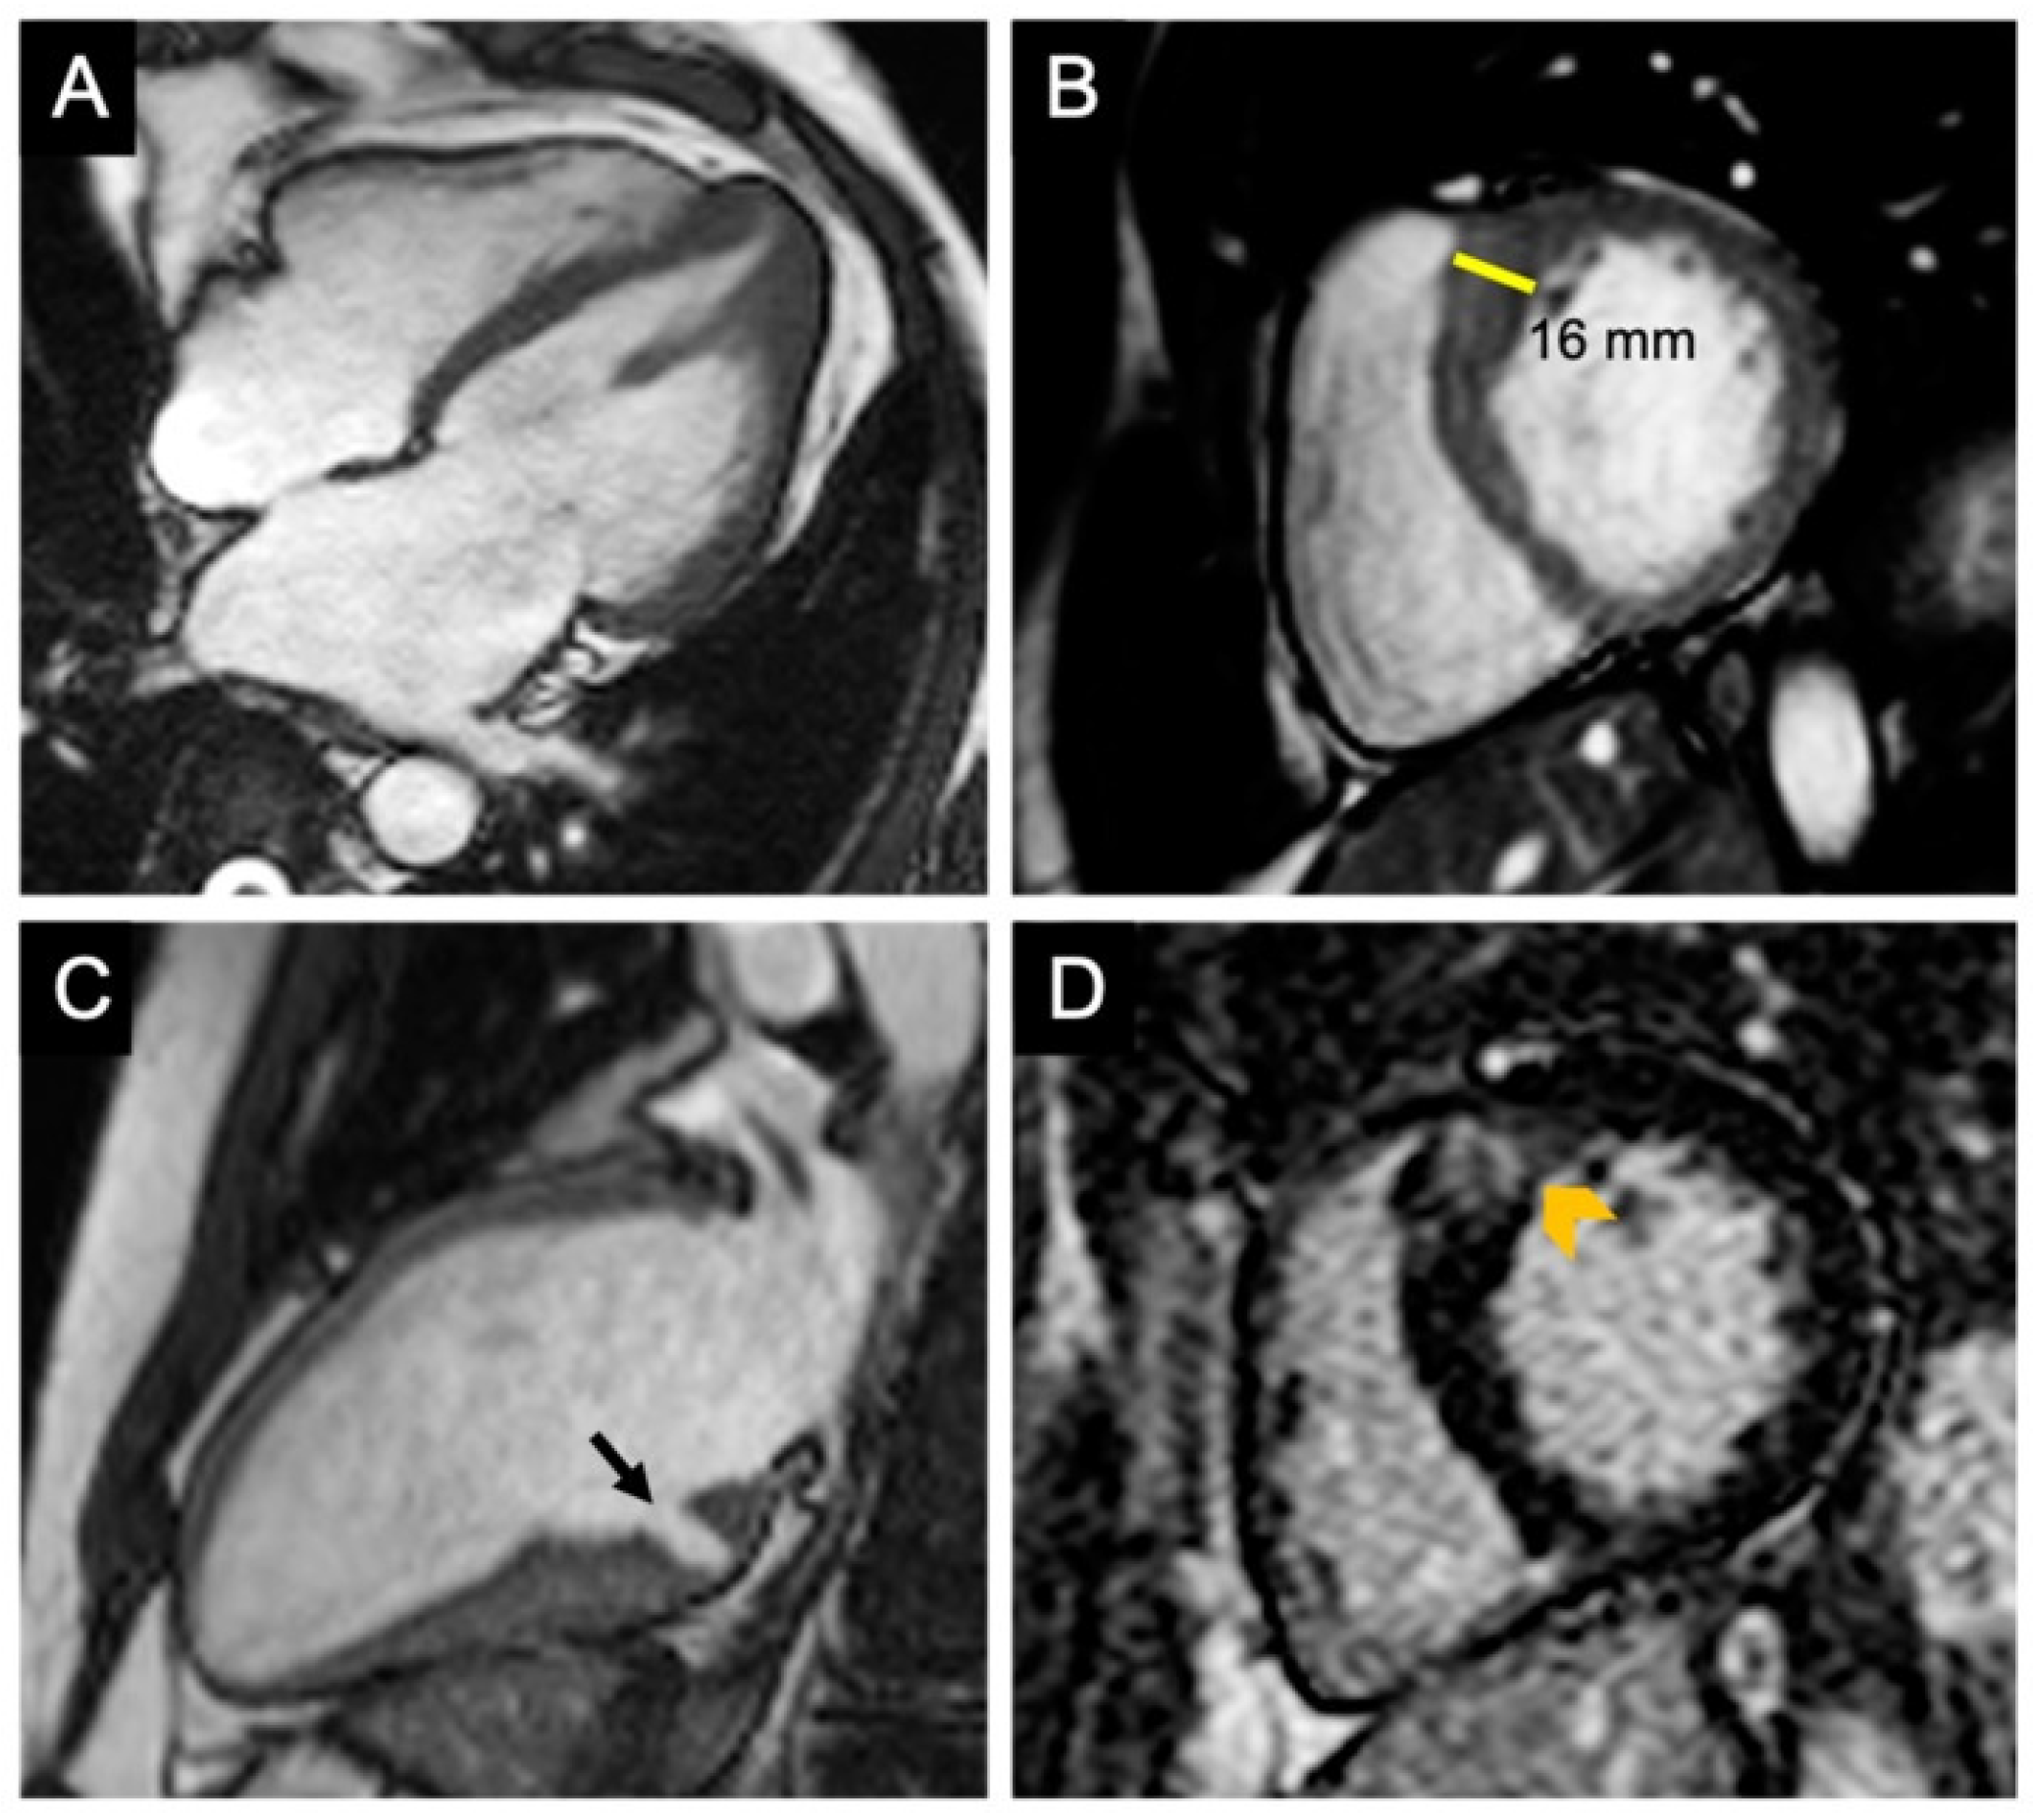

3.4. CMR Evaluation of Apical Aneurysm

3.5. CMR Evaluation of LVOT Obstruction

3.6. CMR Evaluation of Mitral Valve and Papillary Muscles